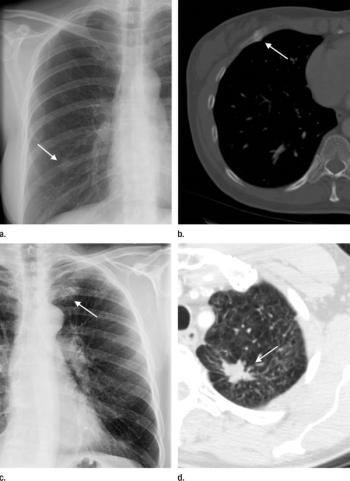

Chest CT follow-ups recommended by radiologists following chest radiograph result in clinically relevant findings.